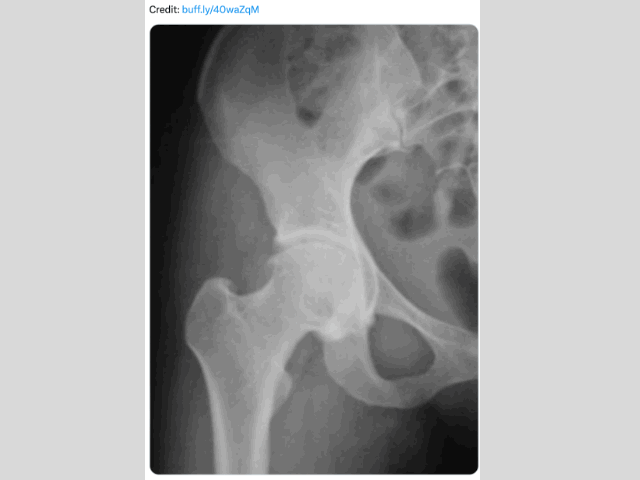

Subtle deformities underpinning Hip Osteoarthritis (OA)..

The Story of Hip OA

..took in

T Rex

,

Academy footballers

Big Brains

+

Deep sockets

, while always centring on

joint

cartilage

The full

Newsletter

#049 to #062

run up to last Christmas tells the story of Hip OA.

Anyone with hip or groin pain over Christmas.. take a look